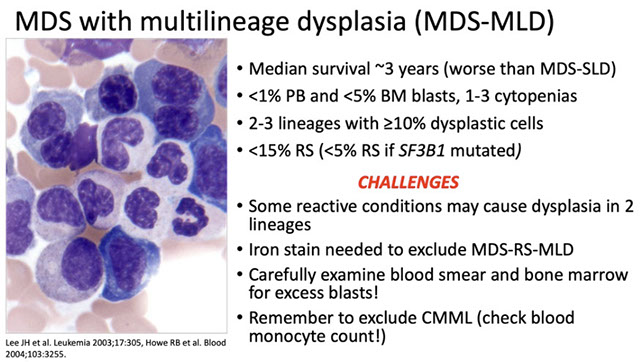

<1% blasts in PB, <5% in BM

Must have >10% of cells in a particular cell line affected to diagnose dysplasia

Must r/o exogenous causes of dysplasia, such as toxins, growth factor tx, viral infx, immunologic / congenital dz, vitamin deficiency / excess (ie zinc supplementation)

If no cytogenetic abnormality present, must wait 6 months to dx

_____________________________________

Px:

Most cases have good long-term survival px, and only a small % progress to AML

- cytogenetic abnormalities are usually those assoc c good px also

-- 90% + of pts live 2 years +, having similar life-expectancies to unaffected population

MDS SLD [3]

Dysmegakaryopoiesis

MDS with ring sideroblasts (MDS-RS)